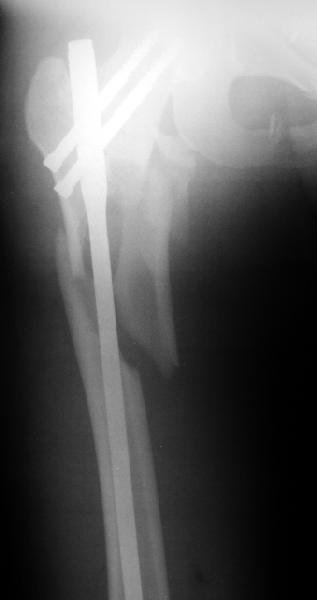

Профиль

Оперировали вчера. Не сказать, что все прошло гладко - вертельная область была расколота и в сагиттальной, и во фронтальной плоскости, гвоздь попал в перелом и сместился кзади, что заметили уже после введения винтов, пришлось все извлечь и переставить. Снимки в приложении. Буду признателен за комментарии.